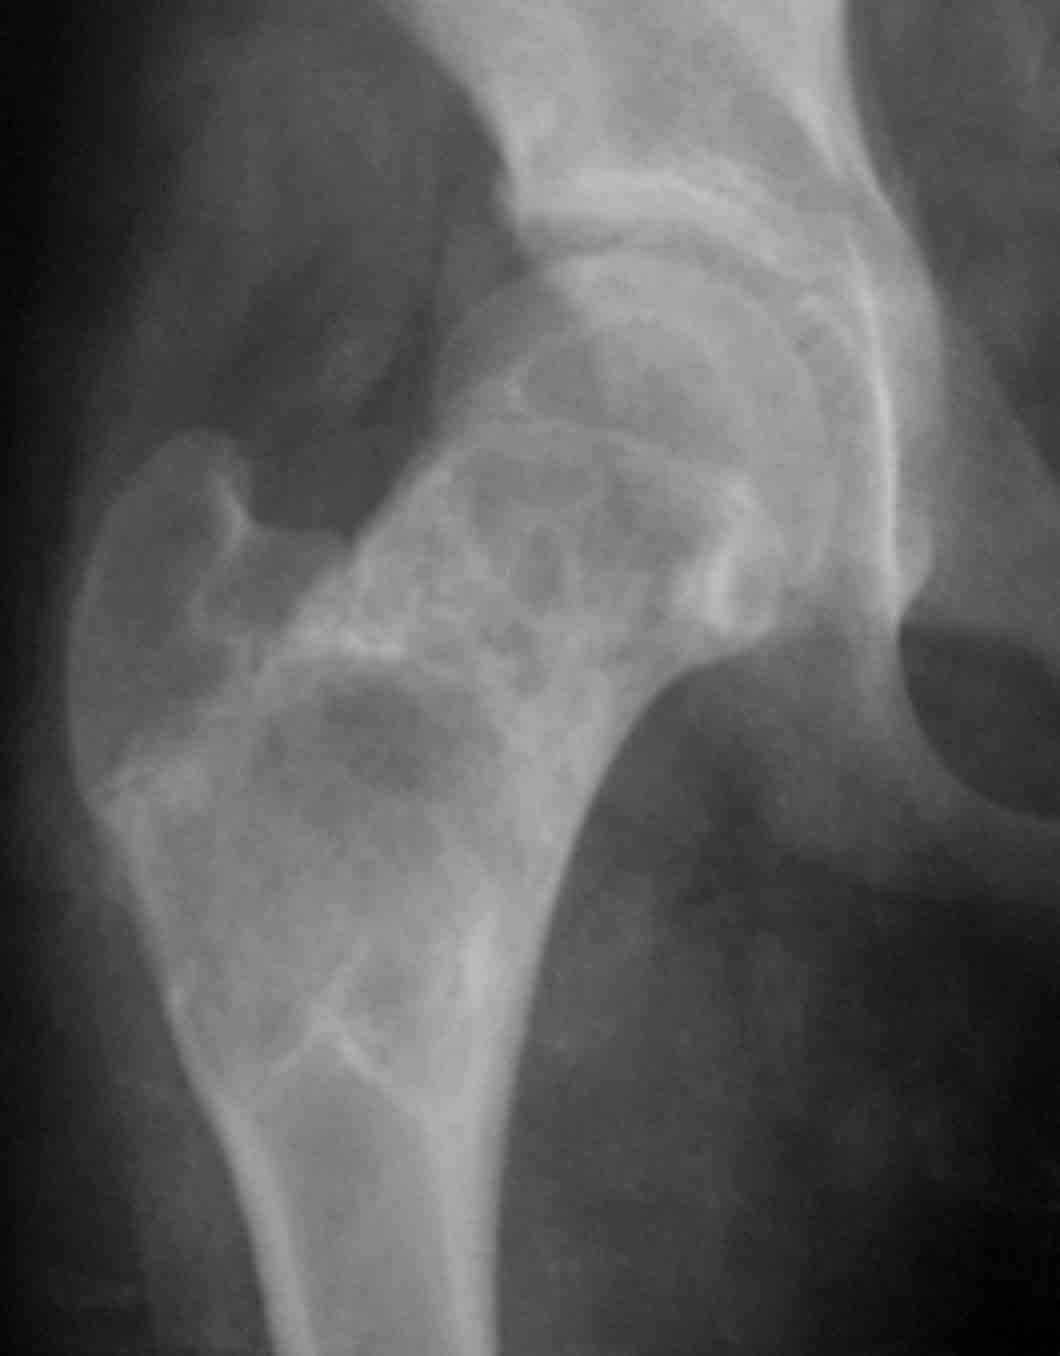

Дабы не уводить в офтопик вопрос о несросшемся переломе бедра, хочу добрым словом упомянутьколлапан - доступный и эффективный российский продукт, который судя по публикациям на форуме не нашел еще должного распространения в повседневной практике. Чтобы не быть обвиненным в рекламе или личной заинтересованности скажу, что работаю я в Казахстане, где большинство последних российских разработок не прошло регистрацию( отдельный вопрос почему?) и коллапан завозят родственники пациентов из соседних сибирских городов. За тридцать лет практики многократно возникали ситуации в которых остро чувствовалась проблема материала для заполнения костных дефектов- от открытых переломов до дефектов при секвестрэктомиии и удаления кистозных опухолей. Риск аутопластики в инфицированную среду или дефицит донорской кости у детей, повсеместное закрытие лабораторий консервации тканей, высокая стоимость зарубежных остеоиндуктивных материалов делают коллапан одним самых доступных материалов в exUSSR \простите за пафос\. В нашем отделении мы применяем коллапан в гранулах с антибиотиком для пристеночной пластики при удалении секвестров при послеоперационных и посттравматических остеитах, при остеосинтезе ложных суставов и заполнении костных дефектов. Коллапан не может применяться в ситуациях где имплантату необходима опорная функция, но это уже другая песня. Привожу пример 15 летнего пациента с обширной фиброзной дисплазией проксимального бедра, которого я оперирован в ноябре 2005, контрольный снимок от 3-2006.

Произведена подвертельная трепанация, кюретаж и рыхлое заполнение гранулами коллапанаГ полости, ушло до 100 куб см гранул. Иммобилизация не проводилась, нагрузка на ногу разрешения через 5 мес, сейчас подросток активно отдыхает на каникулах. Аваскулярный некроз головки вроде не предвидится, думается, что в процессе роста кисты коллатеральное кровообращение сформироваласьдостаточно, о судьбе ростковой зоны можно будет говорить через год. Кстати в одном НИИ ему былапредложена операция эндопротезирования. Первые 2 мес